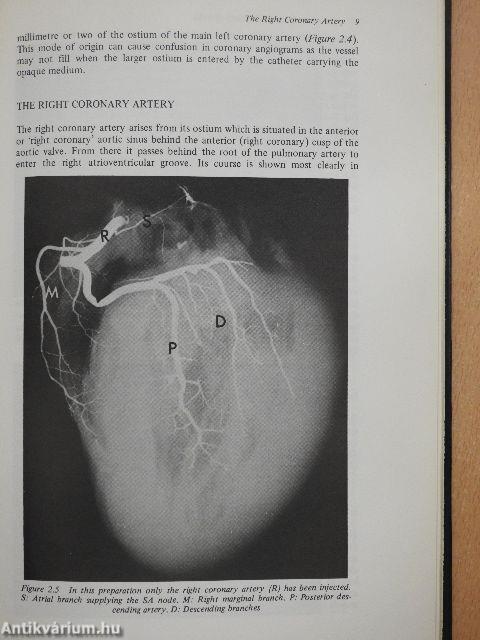

Pathology of Ischaemic Heart Disease

Megjegyzés: Fekete-fehér fotókkal.